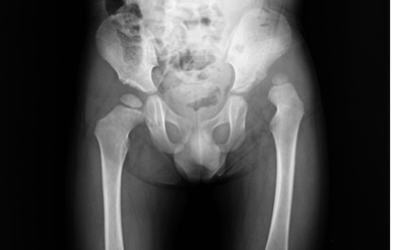

The x-rays show cases of developmental dysplasia of the in the hips that presented after the age of three years. The patients underwent surgery by Dr. Zenios for hip reduction with a pelvic and femoral osteotomy.

Pre-operative